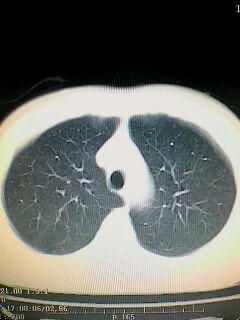

考虑左肺下叶周围型肺癌.图象欠清,请问病人贵更?

考虑左肺下叶周围型肺癌.

左下肺肿块影,深分叶,考虑肺癌。

左下肺球形病灶,考虑:1:球形肺炎;2:周围型肺癌不除外,建议治疗后复查

不排除左肺下叶周围型肺癌可能!建议穿刺活检!

考虑左肺下叶周围型肺癌。

考虑左肺下叶周围型肺癌并阻塞性肺炎。

考虑左肺下叶周围型肺癌